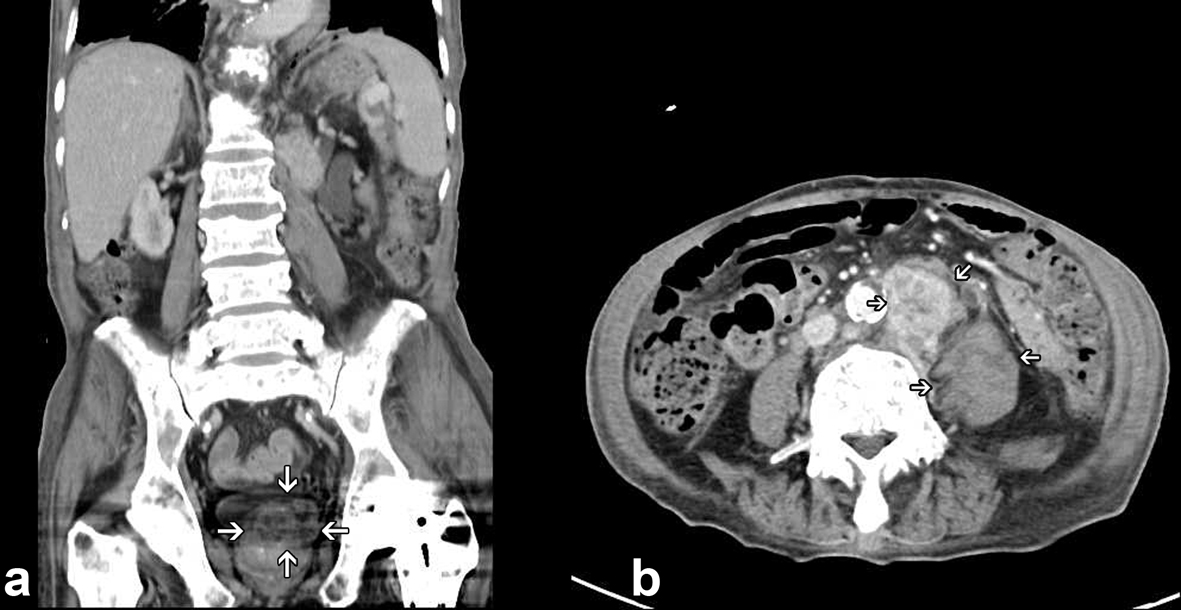

An 82-year-old male patient presented with chest tightness and shortness of breathing for 10 days. His past medical history included hypertension and old pulmonary tuberculosis. He suffered from productive cough for weeks and was referred to our center because of the worsening symptoms of dyspnea and lower leg edema noted over the past few days. On presentation, his consciousness was alert. Body temperature was 37.8 °C. Pulse was 136 per minute regular. Blood pressure was 164/90 mmHg. Oxygen saturation was 88%. Auscultation revealed decreased breathing sounds at left lung field and sonorous rhonchus at right lung field. X-ray of the chest showed left pneumothorax with collapse of left lung, and ground glass opacities in right lung field (Fig. 1), more in favor of inflammatory process at that time. He was admitted under the impression of right lung pneumonia with left pneumothorax and received chest tube insertion and empiric antibiotics treatment. However persistent air leak noted, he then received a chest CT for further survey. A chest CT showed nodular lesions over bilateral lung, with diffuse bone, left lower neck (Fig. 2), left suparclavicular, mediastinum, as well as right hilar (Fig. 3) and lower abdominal lymph nodes metastases. Unknown primary malignancy with bilateral lung metastases, diffuse bony metastases with left supraclavicular and left neck lymph node metastases was impressed and further tissue proof for possible underlying malignancy was recommended. For this reason, an echo guided biopsy with left neck lymph node biopsy was arranged for further study because the surgical intervention was not recommended for the patient due to poor lung function while patient declined bronchoscopy biopsy either. A subsequent neck lymph node biopsy revealed metastatic adenocarcinoma, while immunohistochemical stain for thyroid transcription factor -1(TTF-1), and cytokeratin 20 (CK20) are all negative. Serum tumor markers were examined in an attempt to identify the primary lesion, revealing a PSA level of > 1,000 ng/mL (normal < 4.0 ng/mL) while CEA 2.7 ng/mL (normal < 5.0 ng/mL). Digital rectal examination showed an enlarged and hardened left prostate lobe. An abdomen CT disclosed 4.3 × 3.0 cm ill defined heterogenous mass lesion at lower lobe of prostate (Fig. 4a) with regional and non-regional lymph nodes (Fig. 4b) and bony metastases. The urologist was consulted, and transrectal ultrasonography (TRUS) showed irregular urinary bladder wall thickening with enlargement of prostate, hypoechoic nodule with increased vascularity in left peripheral zone of prostate. Meanwhile the patient refused further tissue proof due to his poor general condition. The pathologist was informed of the elevated serum PSA and further clinical data, then an additional immunohistochemical staining of the left neck lymph node biopsy with P504S was performed as was compared to the regular H&E stain (Fig. 5a), the neoplastic cells expressed P504S diffusely (Fig. 5b), a metastatic adenocarcinoma of prostatic origin was confirmed. However his condition went downhill rapidly, and after thoroughly discussion with the patient and his family, they decided to receive hospice care and refused further intervention.

![]() Click for large image | Figure 4. Enhanced lower abdomen CT showing a 4.3 × 3.0 cm ill defined heterogenous mass lesion over left lobe of prostate (a); with extensive para-aortic and retroperitoneal lymphadenopathy (b). |